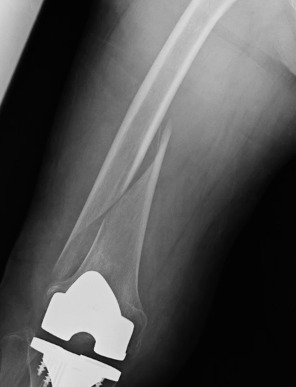

人工膝関節置換術の内容は、傷ついてしまった膝の軟骨や骨を表面的に切り取り、膝の変形を矯正し、金属やセラミック、ポリエチレンなどでできた人工関節に置き換える手術です。手術は1時間程度で終わります。膝がとても痛くて、変形性膝関節症の方やリウマチの方が手術の適応になります。

人工膝関節置換術の手術は、膝痛が消失し歩行能力が改善するというメリットがある反面、いくつかの合併症が伴うことも事実です。そのため、それぞれの合併症に対する予防策をとることがとても大切です。対策を十分とることによって、手術後のリスクを軽減することが可能です。今回の動画を通して、人工膝関節置換術の後に注意すべき合併症について理解していきましょう。